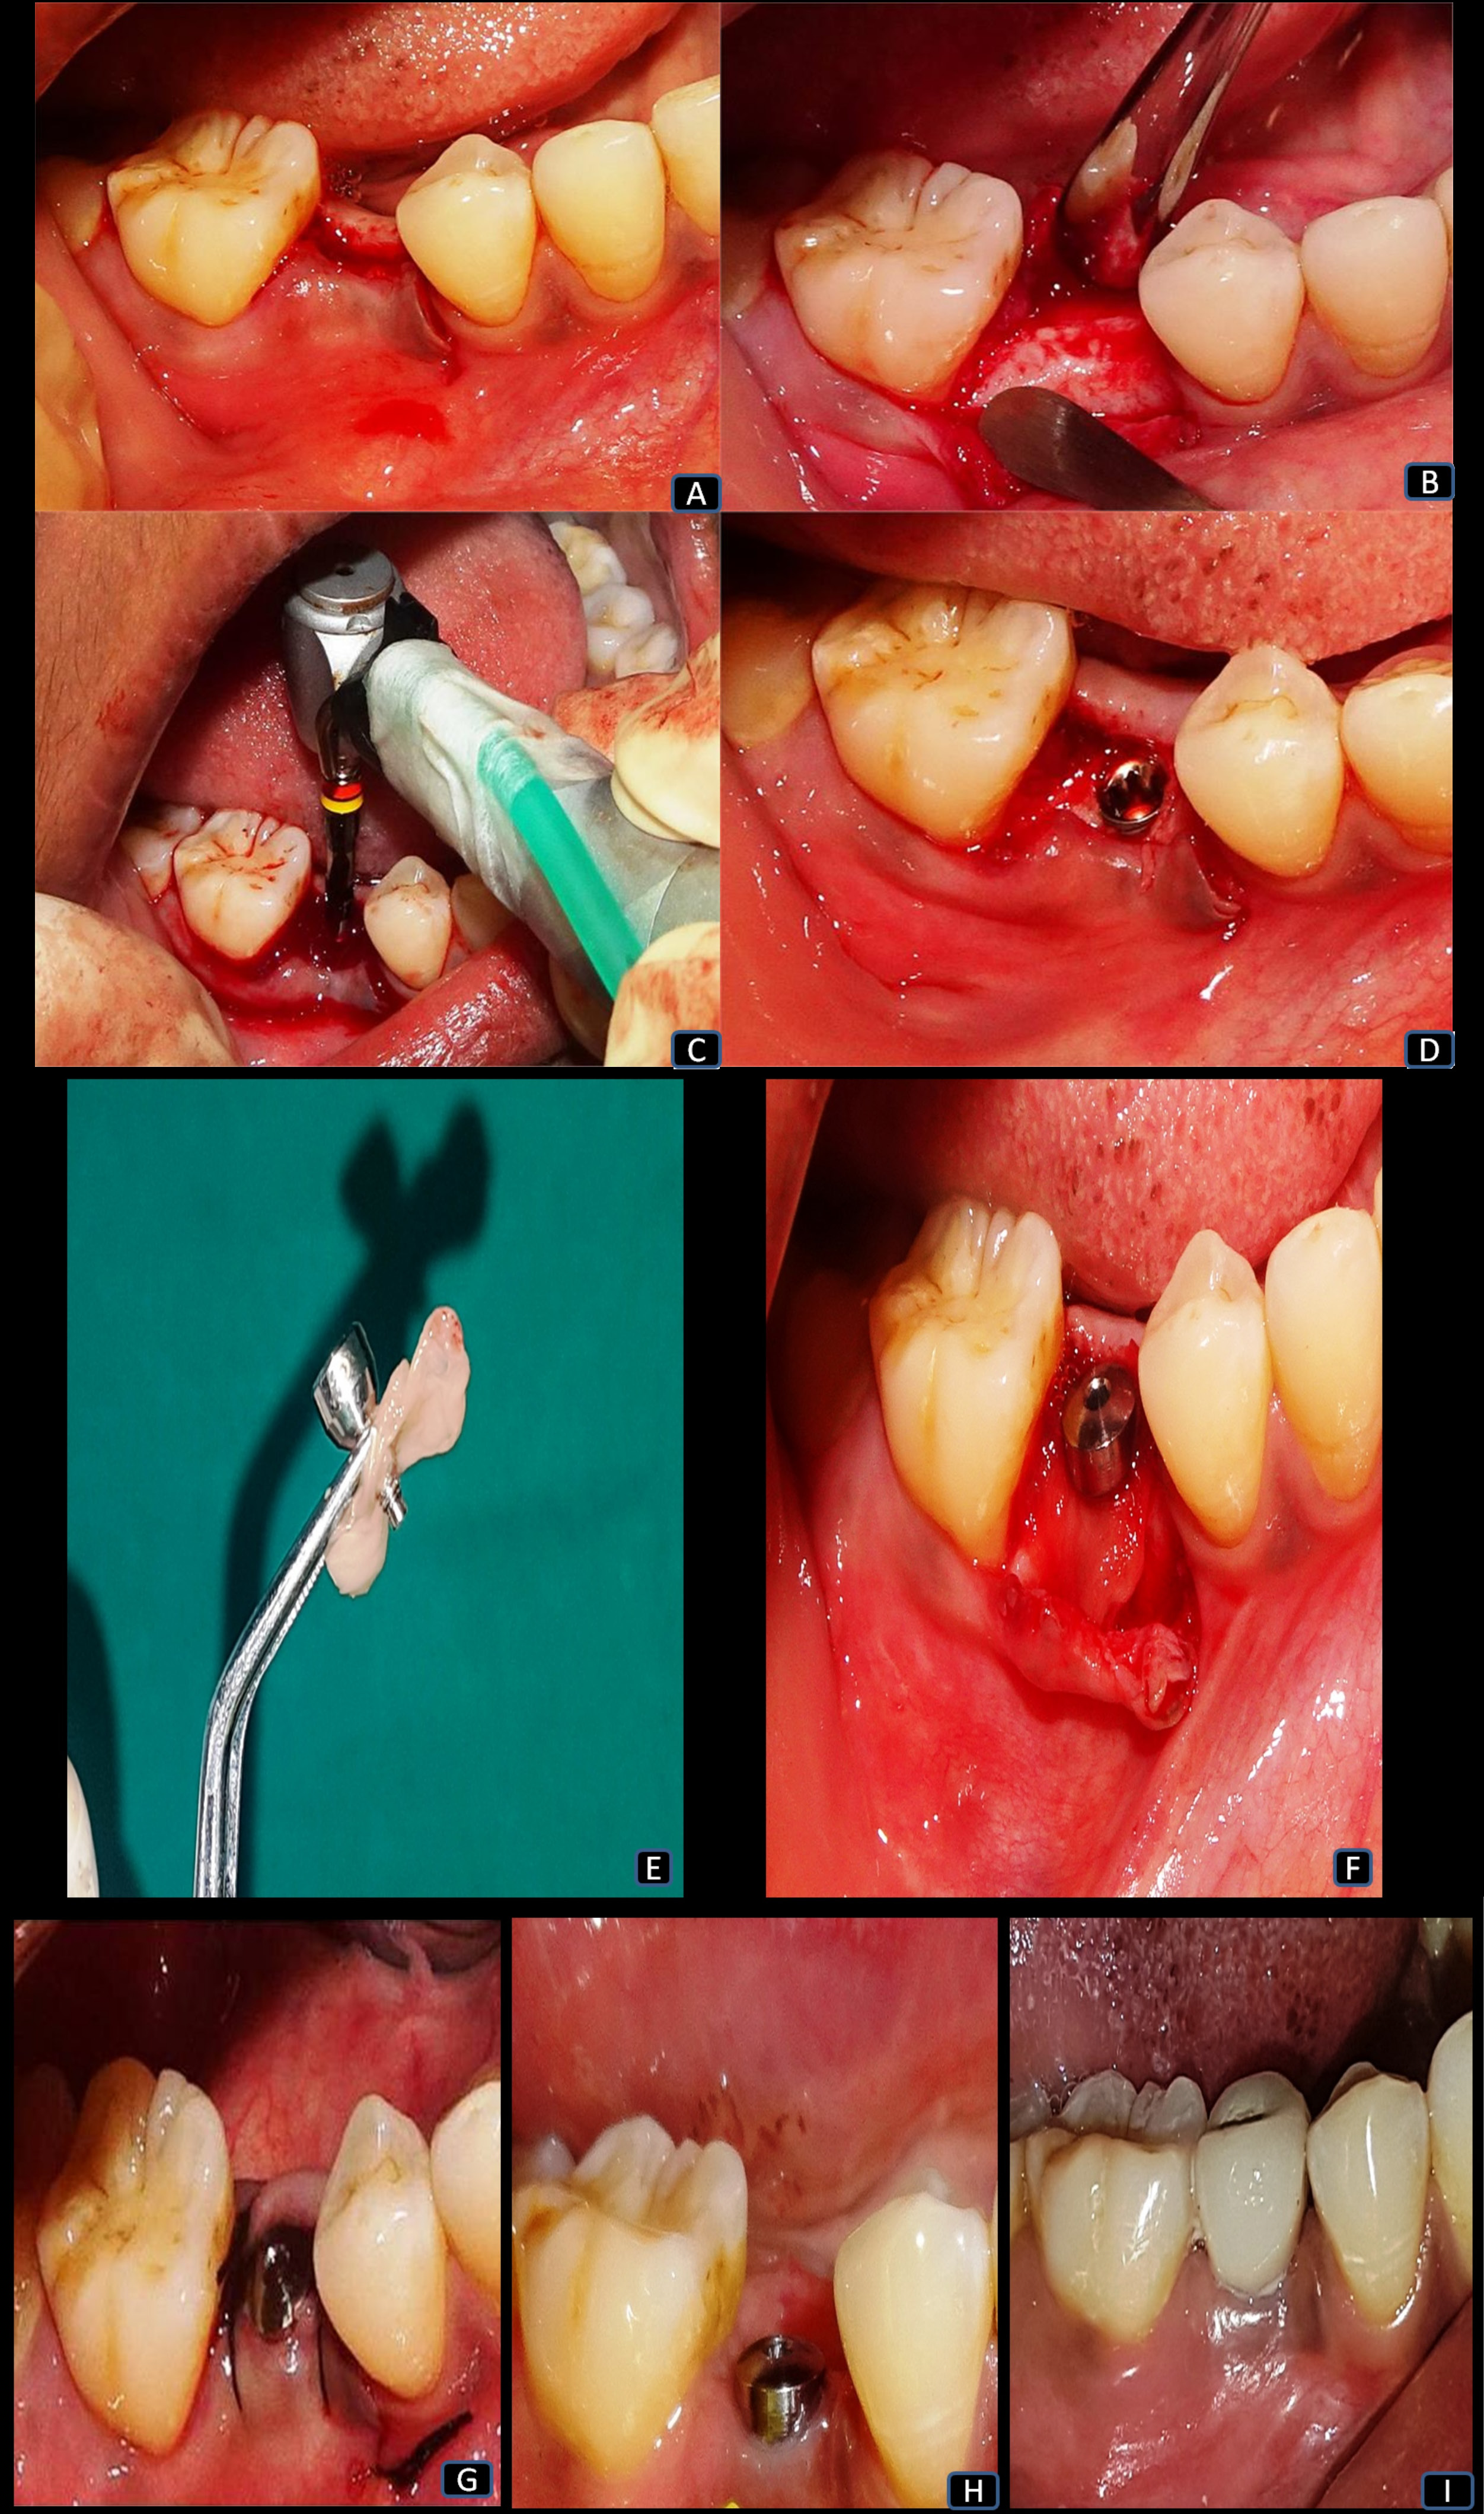

Under adequate local anesthesia, a sulcular mid-crestal incision was made extending to the adjacent tooth (Figure 2), and a full-thickness mucoperiosteal flap was reflected on both the buccal and lingual sides (Figure 2). The initial bone marking used a surgical template. For placing a tapered cylindrical endosseous implant, the osteotomy site was prepared using a series of drills, starting with a 2-millimeter pilot drill, with a speed ranging from 500 to 1,200 rpm under copious irrigation until the desired length was established (Figure 2). Afterward, the implant was installed, and primary stability was assessed using the resonance frequency analysis (RFA) device (Osstell, Gothenburg, Sweden) (Figure 2). Next, we placed the healing abutment on the implant with the use of a torque control device.

In group I, the PRF membrane was placed along with the healing abutment, using the poncho technique to cover the implant (Figure 2).19 The healing abutment was tightened to the PRF membrane so that the PRF membrane covered the implant and the alveolar crestal interface (Figure 2). Subsequently, the flap margins were approximated and sutured in both groups, using non-absorbable 3-0 black silk sutures (Figure 2).

Postoperatively, amoxicillin (500 mg thrice daily) and analgesics (100 mg aceclofenac, 500 mg paracetamol and 15 mg serratiopeptidase twice daily) were prescribed for 5 days, along with 0.2% chlorhexidine gluconate twice daily for 15 days. Postoperative instructions were given to all patients, and they were recalled after 1 week for suture removal. All surgical procedures and postoperative care were carried out by the primary investigator (R.N.S.C.).

At 3 months post-op, the healing cap was replaced with a prosthetic abutment (Figure 2). The restoration was provided with a cement-retained porcelain-fused-to-metal ceramic crown (Figure 2). All outcome measures were evaluated immediately post-op (baseline), and at 3 months and 6 months post-op for both groups. Figure 3 shows the digital IOPA radiographs for both groups.